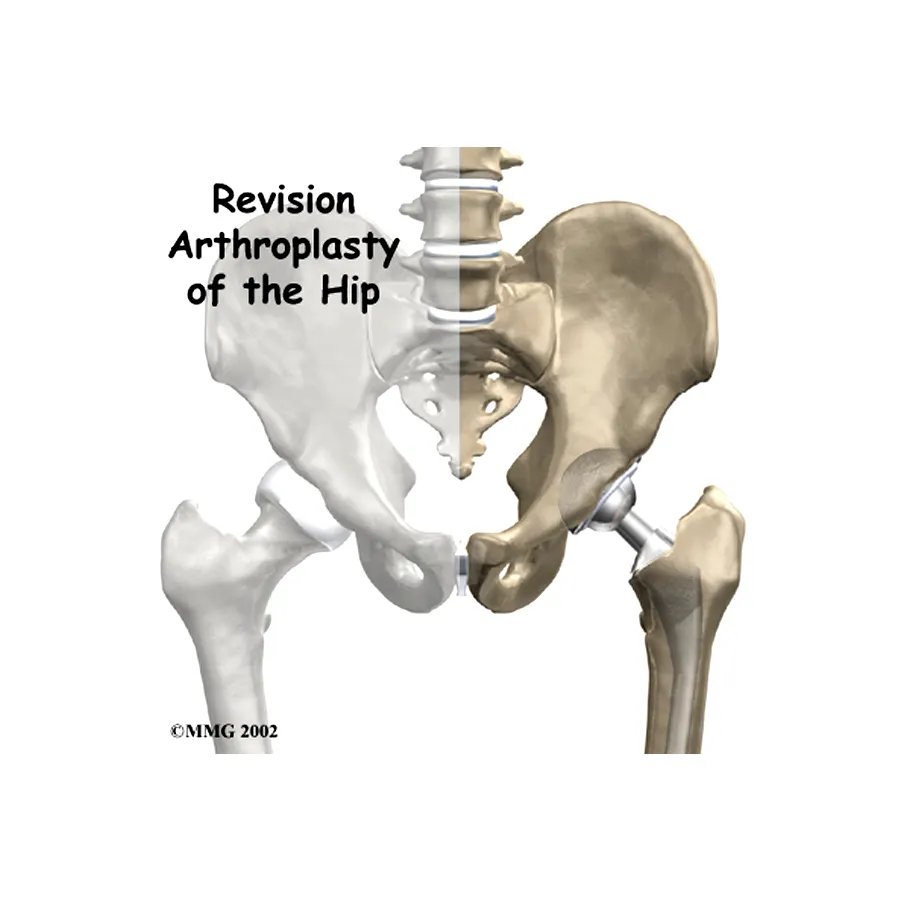

Most trusted, advanced, and affordable knee, hip, elbow, limb salvage surgery in India.

Also cater to revision knee & hip replacement, post-operative care.

Dr Mujahid Saleem is an eminent Orthopaedic surgeon specialising in Joint Replacement Surgery, has exceptional Diagnostic and surgical skills operating now for over 35 years he has performed more than 20,000 surgeries using state-of-the-art techniques for optimum and functional recovery of his patients.